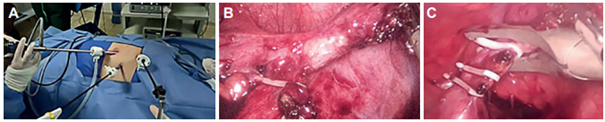

Mediante la laparoscopia se confirmó el situs inversus y un apéndice subseroso en la fosa iliaca izquierda, inflamado en fase fibrinopurulenta, con área de fibrosis y paredes severamente engrosadas en la punta, emplastronado con epiplón. Se llevó a cabo la liberación del apéndice y se completó la apendicectomía sin complicaciones (Figura 1). El paciente tuvo adecuada evolución postoperatoria y se dio egreso al siguiente día. Se confirmó el diagnóstico de apendicitis mediante el estudio histopatológico.